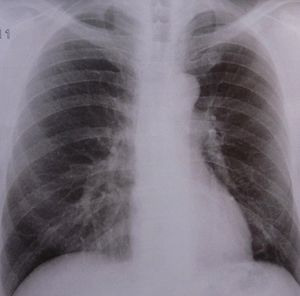

Lungen-Röntgen: Tuberkulose-Resistenzen nehmen zu (Foto: pixelio.de, D. Schütz) |